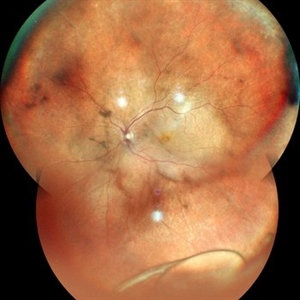

Choroidal Hemangioma Choroidal HemangiomaJan 29 2023 by Anjana Mirajkar, MS Ophthalmology Widefield color image (montage) of RE of a 25 year old female with RE exudative retinal detachment with subretinal mass most likely a Choroidal Hemangioma with fronds of vessels noted inferiorly. Photographer: Dr. Anjana Mirajkar -Retina Foundation, Ahmedabad Condition/keywords: choroidal hemangioma

Choroidal Hemangioma Choroidal HemangiomaJan 29 2023 by Anjana Mirajkar, MS Ophthalmology Widefield color image of RE of a 25 year old female with RE exudative retinal detachment with subretinal mass most likely a Choroidal Hemangioma with fronds of vessels noted inferiorly. Photographer: Dr. Anjana Mirajkar -Retina Foundation, Ahmedabad Condition/keywords: choroidal hemangioma